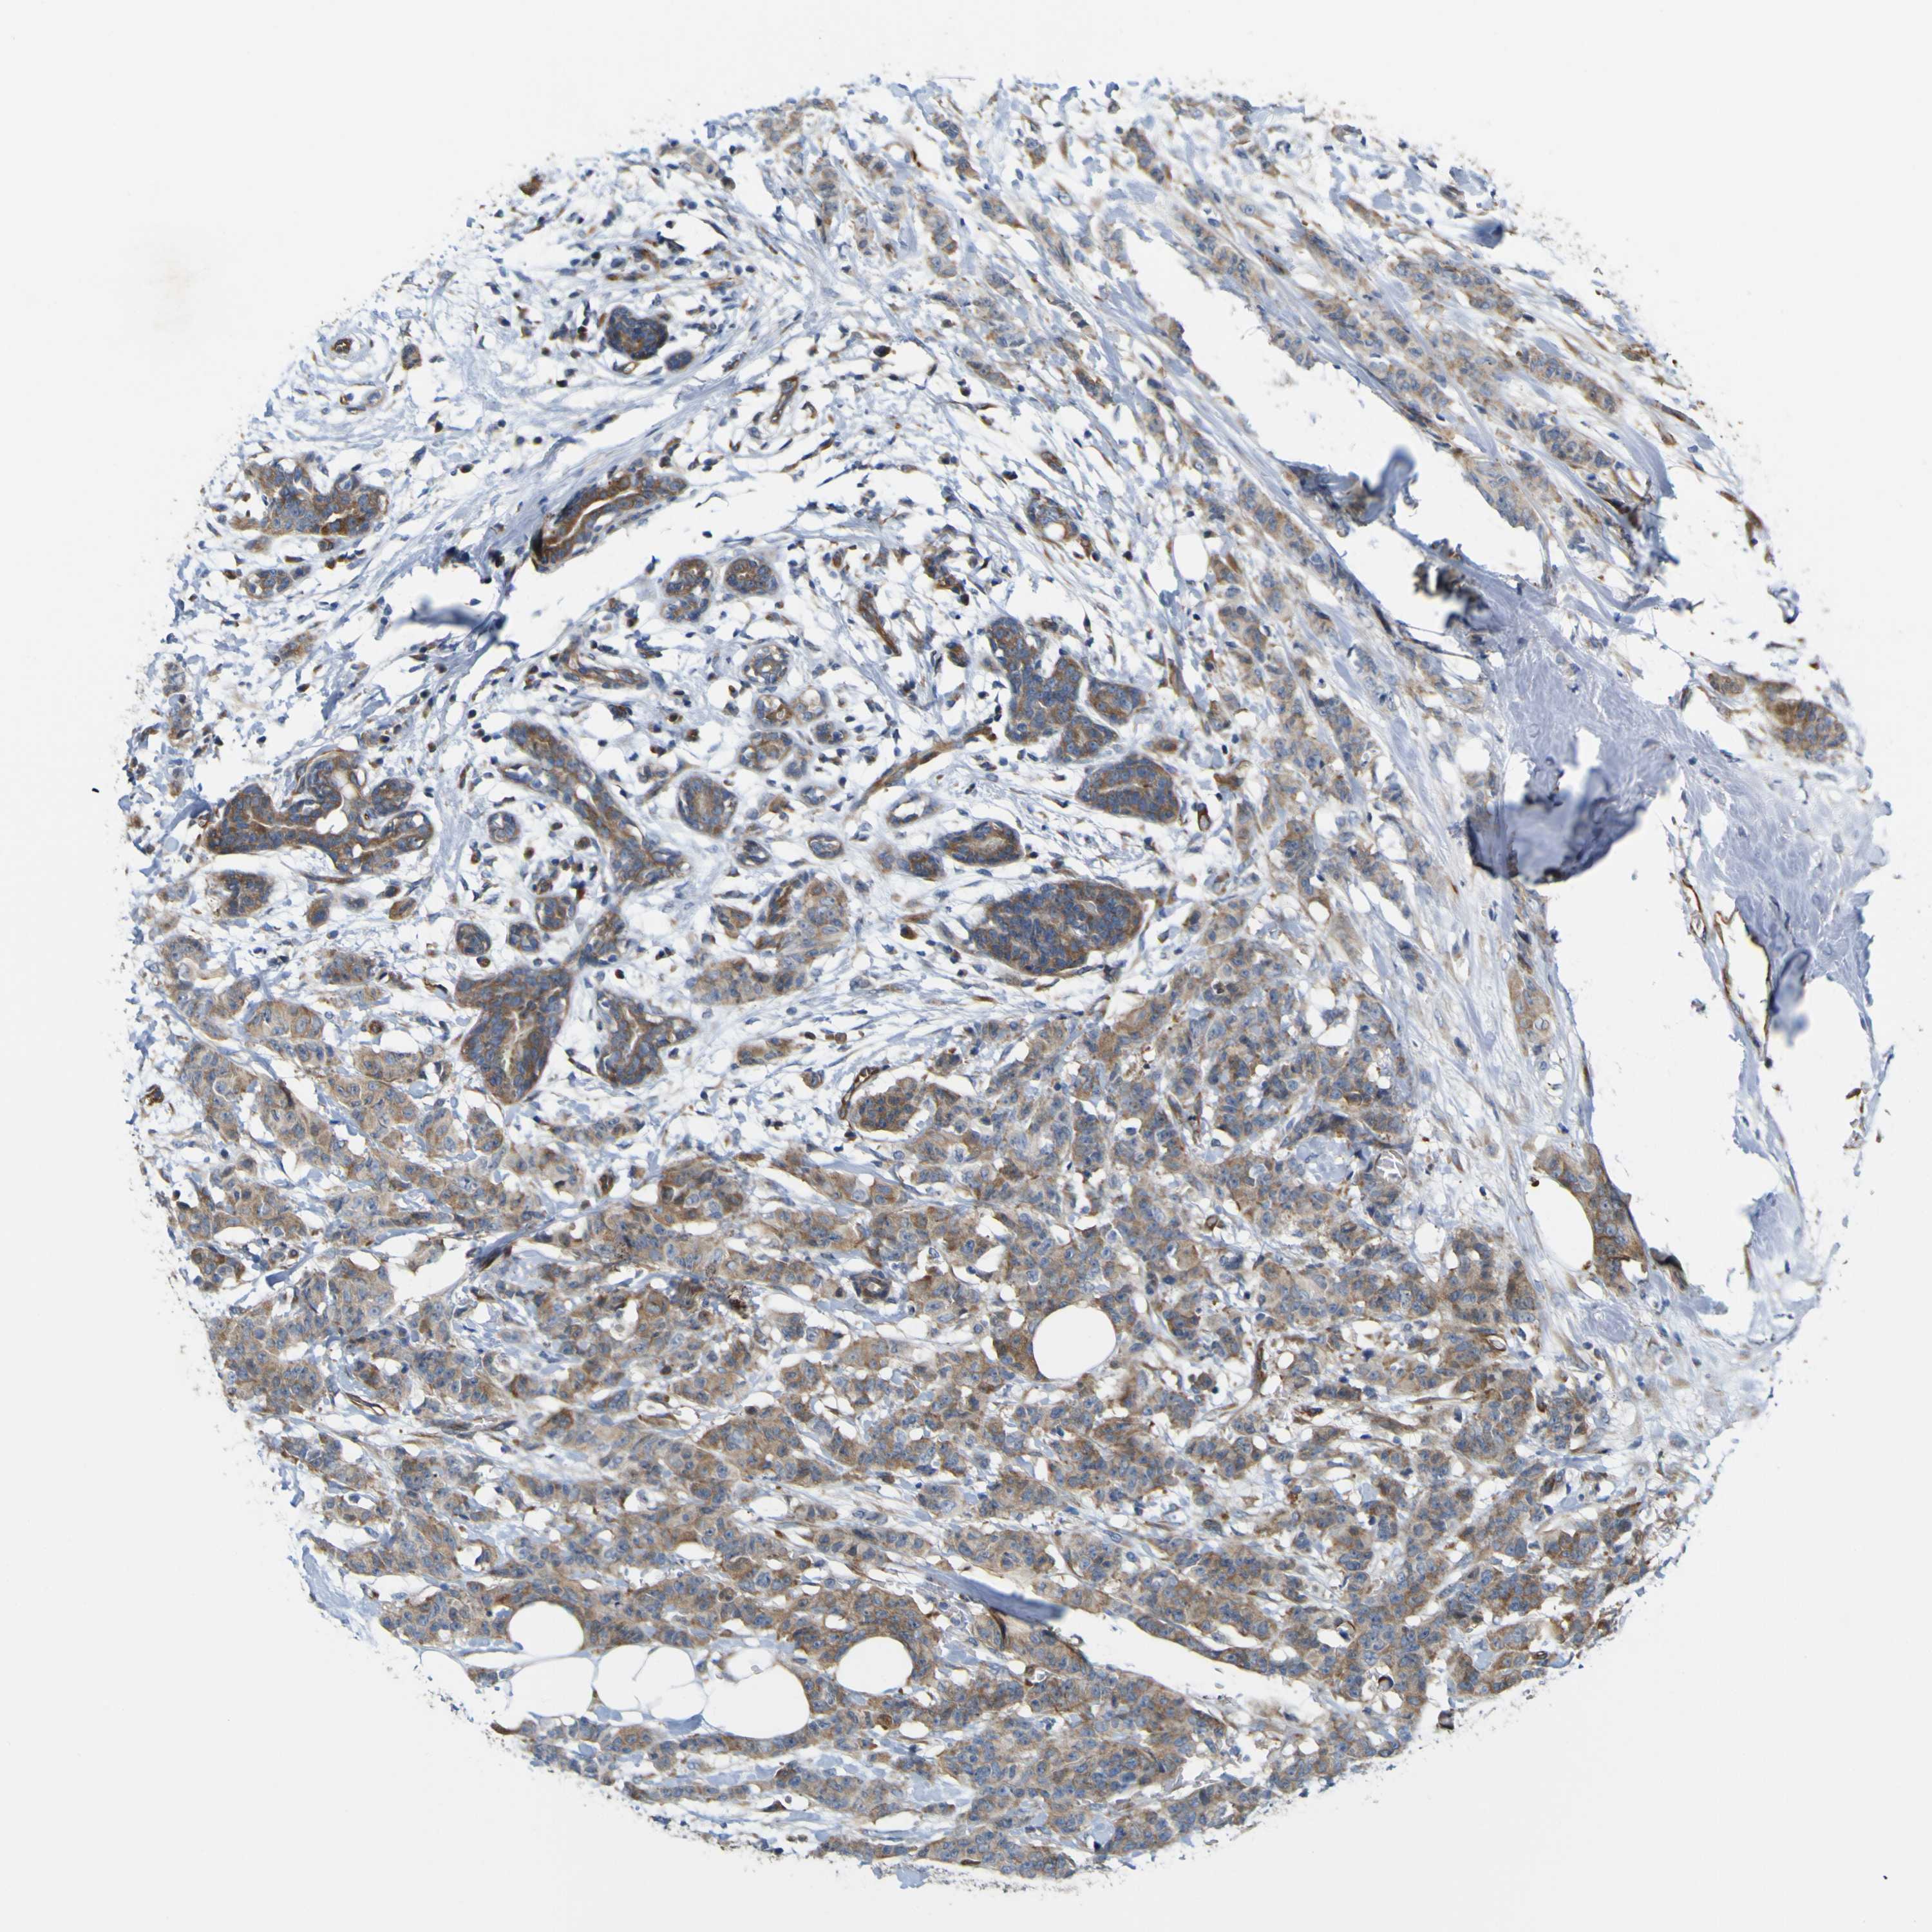

CANCER BREAST CANCER Show tissue menu

BRCA TCGA BRCA VALIDATION PROTEIN EXPRESSION